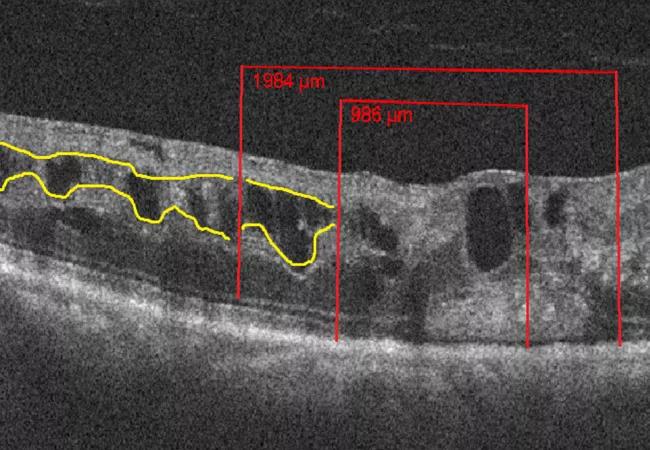

DRIL is defined as the extent to which there is a failure in the recognition of any of the demarcations between the ganglion cell-inner plexiform layer complex, inner nuclear layer, and outer plexiform layer on optical coherence tomography (OCT). This is demonstrated in Figure 1 where yellow lines course through the areas of normal demarcation and stop at those areas with poor demarcation.

We used a presence or absence approach to score DRIL across three regions on the horizontal OCT line scan at baseline, six months, and 12 months. Figure 1 demonstrates how the horizontal line scan was broken down into regions. At six and 12 months, DRIL scores were further evaluated for stable, increasing or decreasing DRIL burden.

Figure 1. Spectral domain OCT (SD-OCT) representing the regional division of the SD-OCT outlined by red lines, and the inner retinal interfaces highlighted by yellow lines that disappear in the areas of DRIL in two representative cases. The top two images are from a patient with a BRVO and the bottom two images are from a patient with a CRVO. Both cases exhibit intraretinal fluid and DRIL in all three regions on SD-OCT and on reverse gray-scale SD-OCT.